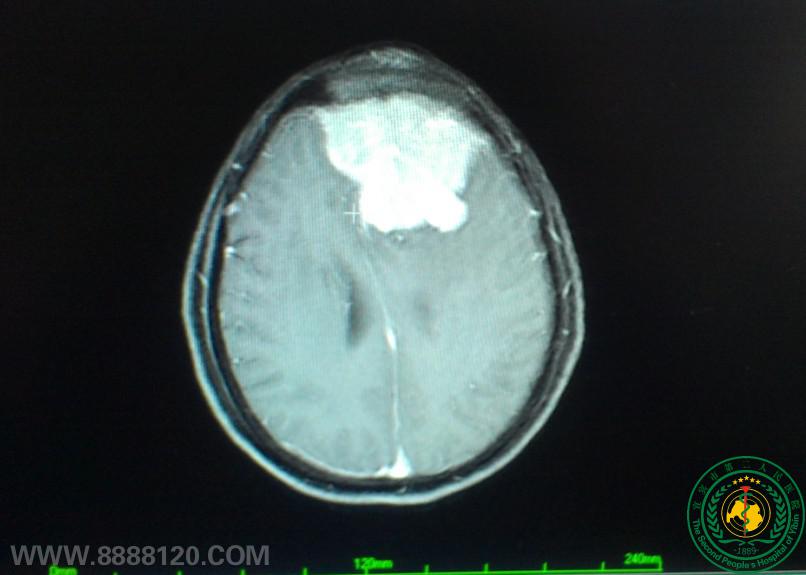

我科顺利完成颅内巨大脑膜瘤一例

我科顺利完成颅内巨大脑膜瘤一例5839